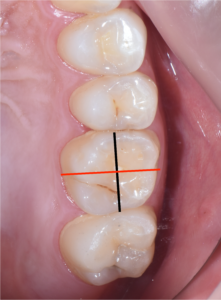

今回歯の上部は健全な部分がたくさん残っているので、上から直径3ミリほどの小さな穴を開けそこから、根の内部の吸収部を除去しようと試みました。